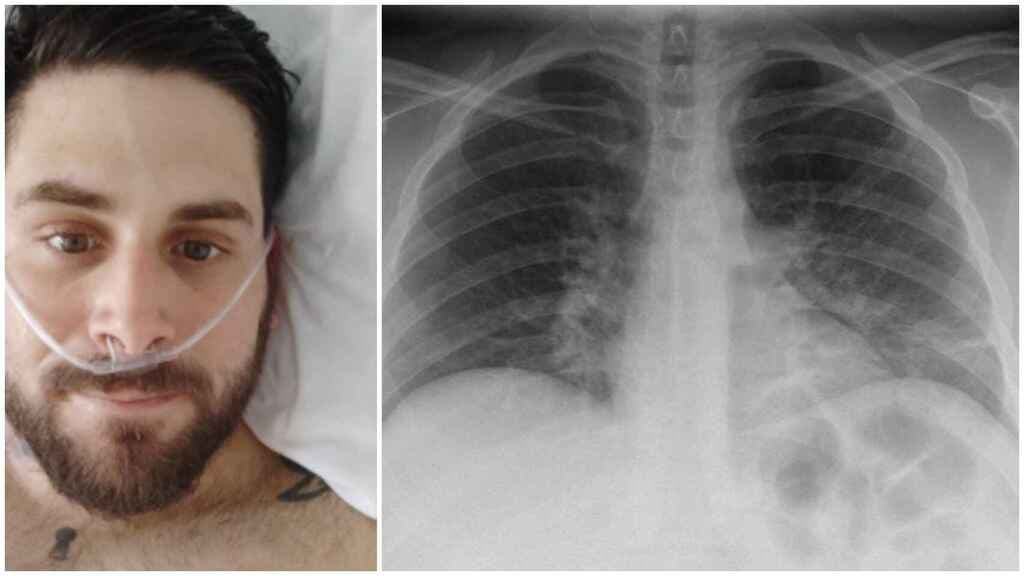

México.-Los órganos más dañados de los pacientes que se recuperan de Covid-19 son los pulmones, es por ello que la UNAM impartirá talleres de rehabilitación para que las personas que han tenido coronavirus, puedan mejorar su respiración.

El objetivo es mostrar ejercicios funcionales para los sobrevivientes del coronavirus mediante la respiración diafragmática-intercostal o profunda, muy útil para recuperar la capacidad pulmonar.